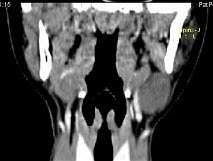

女,16岁,发现左颈部肿块两年,CT如图所示,最可能的诊断为()。

A、囊状水瘤

B、咽部神经鞘瘤

C、咽旁脓肿

D、左侧鳃裂囊肿

E、囊性转移癌

D